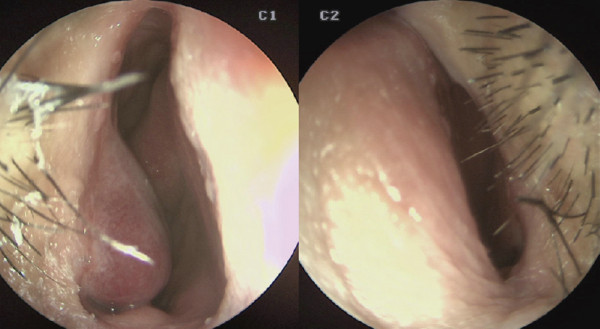

![]()

수술 전 비내시경. 비중격이 전체적으로 좌측으로 만곡되어 C-shape

deviation이 확인되었다. 미단부 변형으로 인해 좌측 비밸브 협착이 보였다.

비중격 만곡은 CT보다 내시경상에서 더 심하게 나타났다

내시경 검사에서는 CT에서보다 더 심한 비중격 만곡이 관찰되었으며, 비밸브 협 착이 보여 비중격 및 비밸브 교정술,

하 비갑개 점막 절제술을 계획하였다.